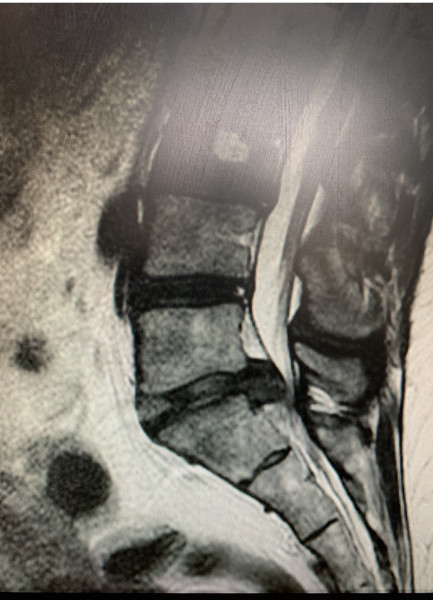

anotherdaynotanotherdollar · 30/04/2022 15:01

This is how it is now. If I were you I would defo get a second opinion.

Could this be cauda equina